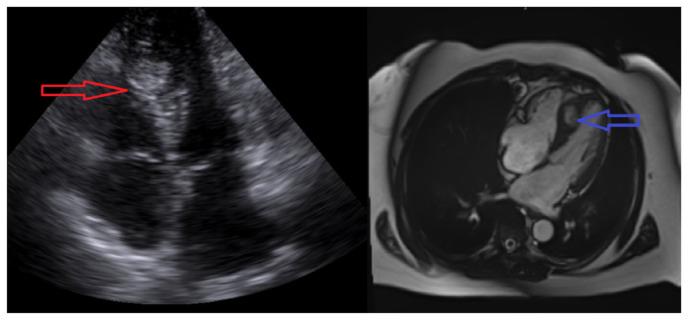

A Rare Discovery of Neuroendocrine Tumor: Cardiac Mass.

Carcinoid tumors are rare, slow-growing neoplasms of neuroendocrine origin commonly affecting the gastrointestinal or respiratory system. They metastasize to lymph nodes and the liver based on their lymphatic and venous drainage of their tissue of origin. Metastasis to the heart is exceedingly rare accounting for <2 % of cases. Exceedingly rare is the incidental detection of cardiac carcinoid metastasis as the initial presentation of carcinoid syndrome. Here, we describe a case of metastatic cardiac carcinoid detected during a routine echocardiogram done for evaluation of a systolic murmur.